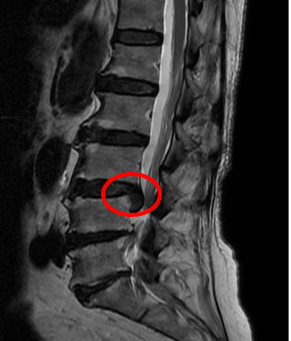

在家人陪同下,她来到了姜为民主任的门诊,在耐心地询问病史及细致的查体后,姜主任判断出这多半是“腰椎间盘突出”在作祟。腰椎磁共振检查结果也证实了他的诊断。

(巨大的椎间盘压迫神经)

对于椎间盘突出症,轻者可以采取保守治疗,但像王奶奶这样的巨大椎间盘突出,症状又非常严重的,保守治疗很痛苦,手术治疗非常必要,由于岁数大,如果采取常规的开放手术创伤及风险都较大,因此,微创手术是最佳选择。在跟王奶奶及家属充分沟通后,姜主任团队为老人施行了一种简称为UBE的手术,术后效果立竿见影,困扰了王奶奶3个多月的症状消失了。